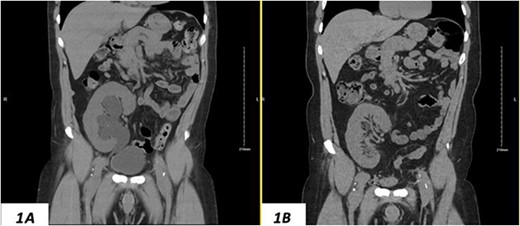

Despite a new onset proteinuria of 50 mg/dl, he continued to have a good functioning graft with a creatinine level of 93 μmol/l corresponding to an estimated glomerular filtration rate (eGFR) of 78 ml/min/1.73 m2. Nonetheless, he had also been noting an inguinal bugle that becomes more prominent as the day progressed, and it regressed at night. Upon further investigations, an ultrasound of the allograft revealed moderate-to-severe hydronephrosis. Further imaging using computed tomography scan (CT) confirmed the presence of upstream moderate hydronephrosis (Figs 1A and2A) along with a reported herniation of the ureter in a right inguinal hernia, resulting in a focal distal ureteric dilatation of 3.5 cm (Fig. 3A).

(A) Hydronephrosis on preoperative sagittal CT scan showing the reported dilated part of the distal ureter (*), which was correctly identified intraoperatively as a sliding dome of the bladder; note the relationship to the pubic bone; (B) significant improvement of hydronephrosis on the 10-month postoperative image.

The hydronephrosis significantly improved in the 1-year follow-up imaging (Figs 1–3B). The patient continues to enjoy satisfactory graft function with no hernia recurrence. As of July 2023, the patient had further improvement in graft function reflected via a serum creatinine of 76 μmol/l reflecting a eGFR of 99 ml/min/1.73 m2 and 10 mg/dl of proteinuria.